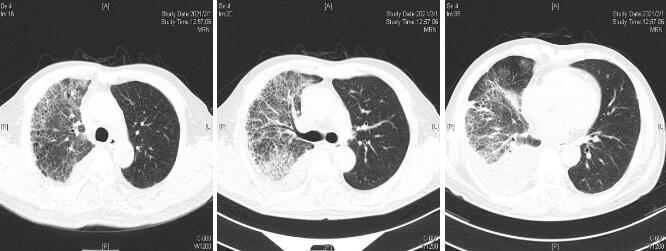

患者经过近1周治疗,临床症状较前好转,心衰纠正,炎症指标明显下降,于1月31日体温正常后转普通病房。感染方面美平降级为头孢派酮舒巴坦,继续多西环素治疗。2月2日外送标本DNA测序鉴定为Balneatrix alpica,即阿尔卑斯浴者菌。后续患者出现胸膜炎性胸痛,间断气促,复查肺部CT提示右侧胸腔积液量增多,给予穿刺引流,胸水外送经DNA鉴定报高山巴氏发菌,即Balneatrix alpica,至此患者感染的病原菌明确,考虑此菌为少见菌,对抗菌药物敏感性较高,后续抗生素方案降解为左氧氟沙星500 mg/d,经治疗3周后患者出院,后期随访追踪无不适。

| 图 4 3月23日(出院1个月后复查胸部CT平扫) |